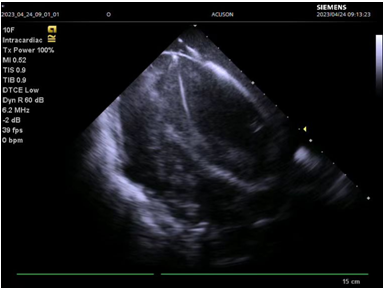

图三:心腔内超声指导下成功穿刺房间隔

此例手术由姚晓伟主任医师、韩稳琦主治医师、赵永勇主治医师通过心腔内超声指导下进行,通过心腔内超声精准构建心脏模型、直视下穿刺房间隔,后通过心腔内超声及左心房造影寻找狭窄的二尖瓣瓣口,并指引二尖瓣球囊扩张导管顺利经狭窄的二尖瓣口至左心室,在心腔内超声的指引下选择最佳位置以26mm球囊导管反复扩张狭窄的二尖瓣。术后第二天复查心脏超声,患者二尖瓣瓣口面积由术前0.67cm2扩大到术后1.69cm2,二尖瓣跨瓣压差由术前22mmHg降低至术后的16mmHg,左房前后径由术前94mm减小至术后92mm,左房左右径由术前109mm减小至术后102mm,并且球囊扩张后未引起明显的二尖瓣反流,患者心功能明显改善,自觉症状明显好转出院。